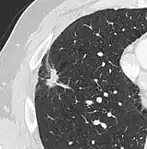

subpleural nodule.[9]

Round well-delineated solid lung nodule with smooth border.[9]

Lobulated nodule.[9]

Spiculated lung nodule.[9]

A "notch sign".[9]

A triangular perifissural node can be diagnosed as a benign lymph node.[9]